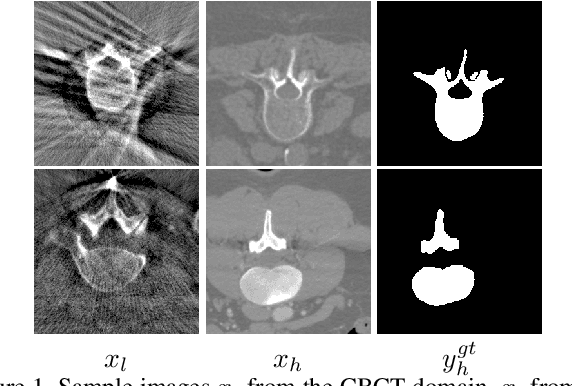

Abstract:We investigate the unsupervised learning of the vertebra segmentation, artifact reduction and modality translation of CBCT images. To this end, we formulate this problem under a unified framework that jointly addresses these three tasks and intensively leverages the knowledge sharing. The unsupervised learning of this framework is enabled by 1) a novel shape-aware artifact disentanglement network that supports different forms of image synthesis and vertebra segmentation and 2) a deliberate fusion of knowledge from an independent CT dataset. Specifically, the proposed framework takes a random pair of CBCT and CT images as the input, and manipulates the synthesis and segmentation via different combinations of the decodings of the disentangled latent codes. Then, by discovering various forms of consistencies between the synthesized images and segmented , the learning is achieved via self-learning from the given CBCT and CT images obviating the need for the paired (i.e., anatomically identical) groundtruth data. Extensive experiments on clinical CBCT and CT datasets show that the proposed approach performs significantly better than other state-of-the-art unsupervised methods trained independently for each task and, remarkably, the proposed approach achieves a dice coefficient of 0.879 for unsupervised CBCT vertebra segmentation.